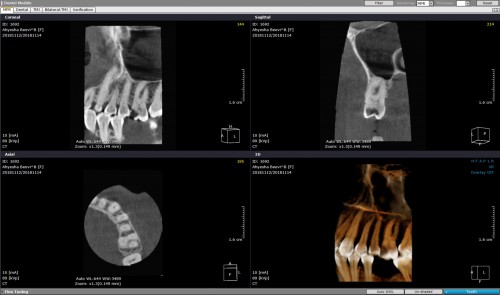

3yr recall of a cracked #36

3yr recall of a cracked #36 with fracture extending into the ML root. When the […]